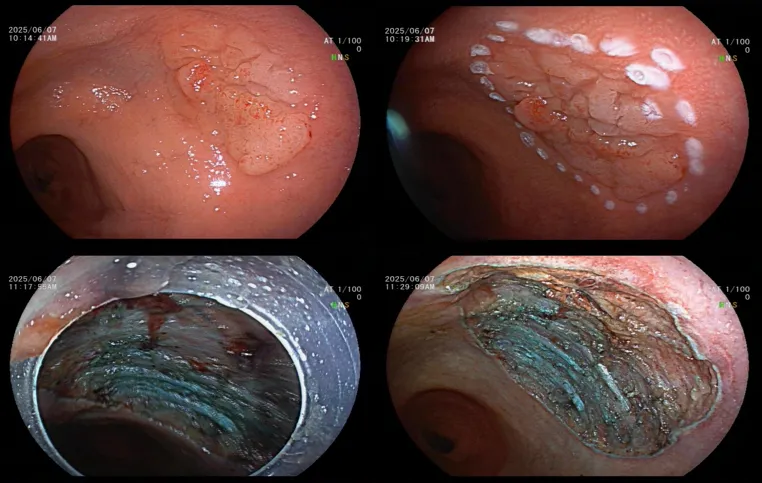

患者胡某,女(nǚ),61歲,因"反複下腹痛1年餘"於2025年5月30日來院就診。結腸鏡檢查發現直腸粘膜隆起(qǐ)病變(LST),患者辦(bàn)理入住(zhù)腫瘤消化科接受內鏡下(xià)ESD治(zhì)療。經充分術前準備及評估,於6月7日在全身麻醉下實施腸鏡下治療。術中發現病灶呈扁平狀,大小約2.0×3.0 cm,表麵顆粒狀,邊界清晰。完成基底注射後,觀察到明顯的抬舉現象。隨後進行(háng)環周切開,完整剝離病(bìng)灶,創麵采(cǎi)用電凝止血,並對部分創麵使(shǐ)用鈦夾進行夾閉處理。切(qiē)除標本(běn)已送(sòng)病(bìng)理檢查。